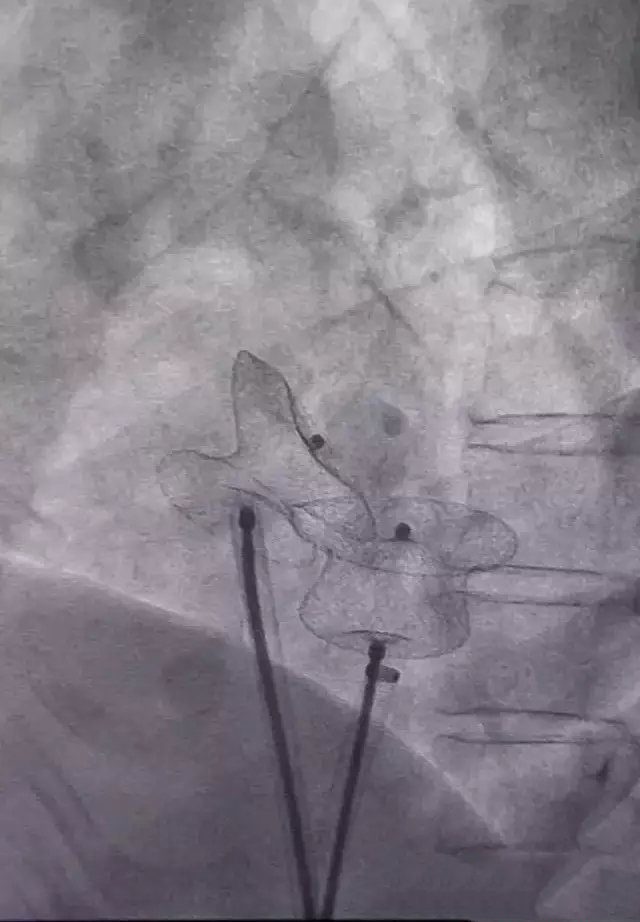

After repeated communication with patients and their families, director Zhang founded the group therapy, according to the patients with transesophageal ultrasonography imaging and cardiac CT images, and Xi'an Jiaotong University 3D printing technology team collaboration, after repeated communication, repeated comparison and research are discussed and decided patients surgical plan, print out the 3D model of heart patients, for patients "tailored" to the appropriate type of occluder.

On August 10 in interventional operation room, with ultrasound room, with the director of the surgical team after 40 minutes is very successfully completed the surgery requires three hours to complete the operation in, and patients also awake to witness this. The operation completed successfully, marking the First Affiliated Hospital success broke the inferior atrial septal defect of the operation area, towards a new level of interventional therapy, is the first case in the country. The patient recovered well and was discharged from hospital after surgery.